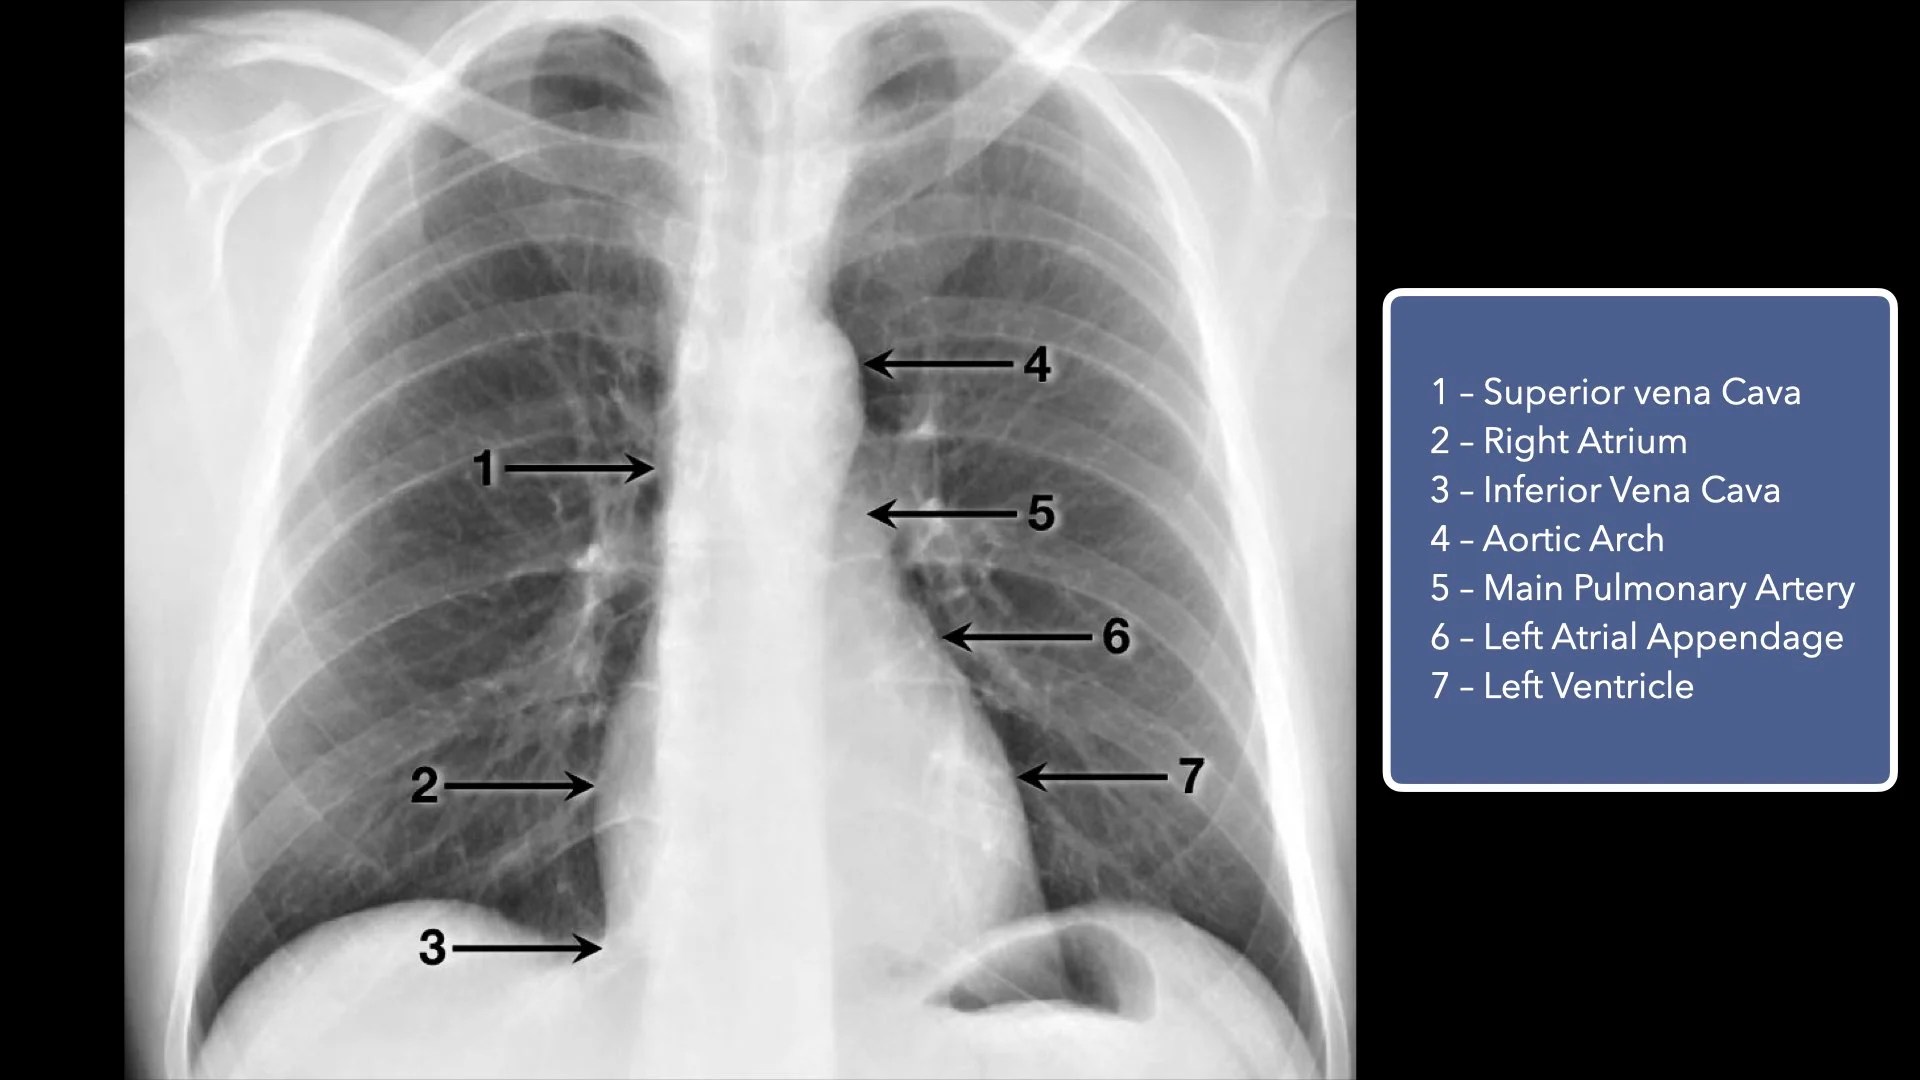

Basic Chest XRay Interpretation Tips and pointers to see it all!

Chest Xray Anatomy Radiology anatomy part 1 prep How to interpret Why Do I Need A Chest X Ray For High Blood Pressure It allows doctors to closely examine your heart, lungs and chest wall. Learn about the tests, criteria, and what to expect for diagnosing pulmonary hypertension, an elevation in the blood pressure of the lungs. Why Do I Need A Chest X Ray For High Blood Pressure.